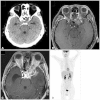

lnflammatory pseudotumor (IPT) is a rare, non-neoplastic inflammatory process. It is most commonly occurs in the orbit, but extension into brain parenchyma is uncommon. In a confirmed case of IPT, most cases show good improvement with steroid theraphy. A 50-year-old man with progressive left-eye visual disturbance and mass lesion was admitted in a hospital. A left orbital mass biopsy revealed what was highly suspected as an inflammatory pseudotumor. Steroid pulse therapy with dexamethasone, radiation therapy, and chemotherapy with amphotericin B were performed, but they were not effective in improving the condition of the patient. Revision open surgery was then performed. A follow-up brain enhancement computerized tomography showed an enlarged mass volume and hydrocephalus with periventricular enhancement. As an additional procedure, ventriculoperitoneal shunt and tuberculosis medication were administered. About 2 weeks later, clinical symptoms and radiologic findings improved. We present a case of intra-cranial IPT and discuss further treatment methods.